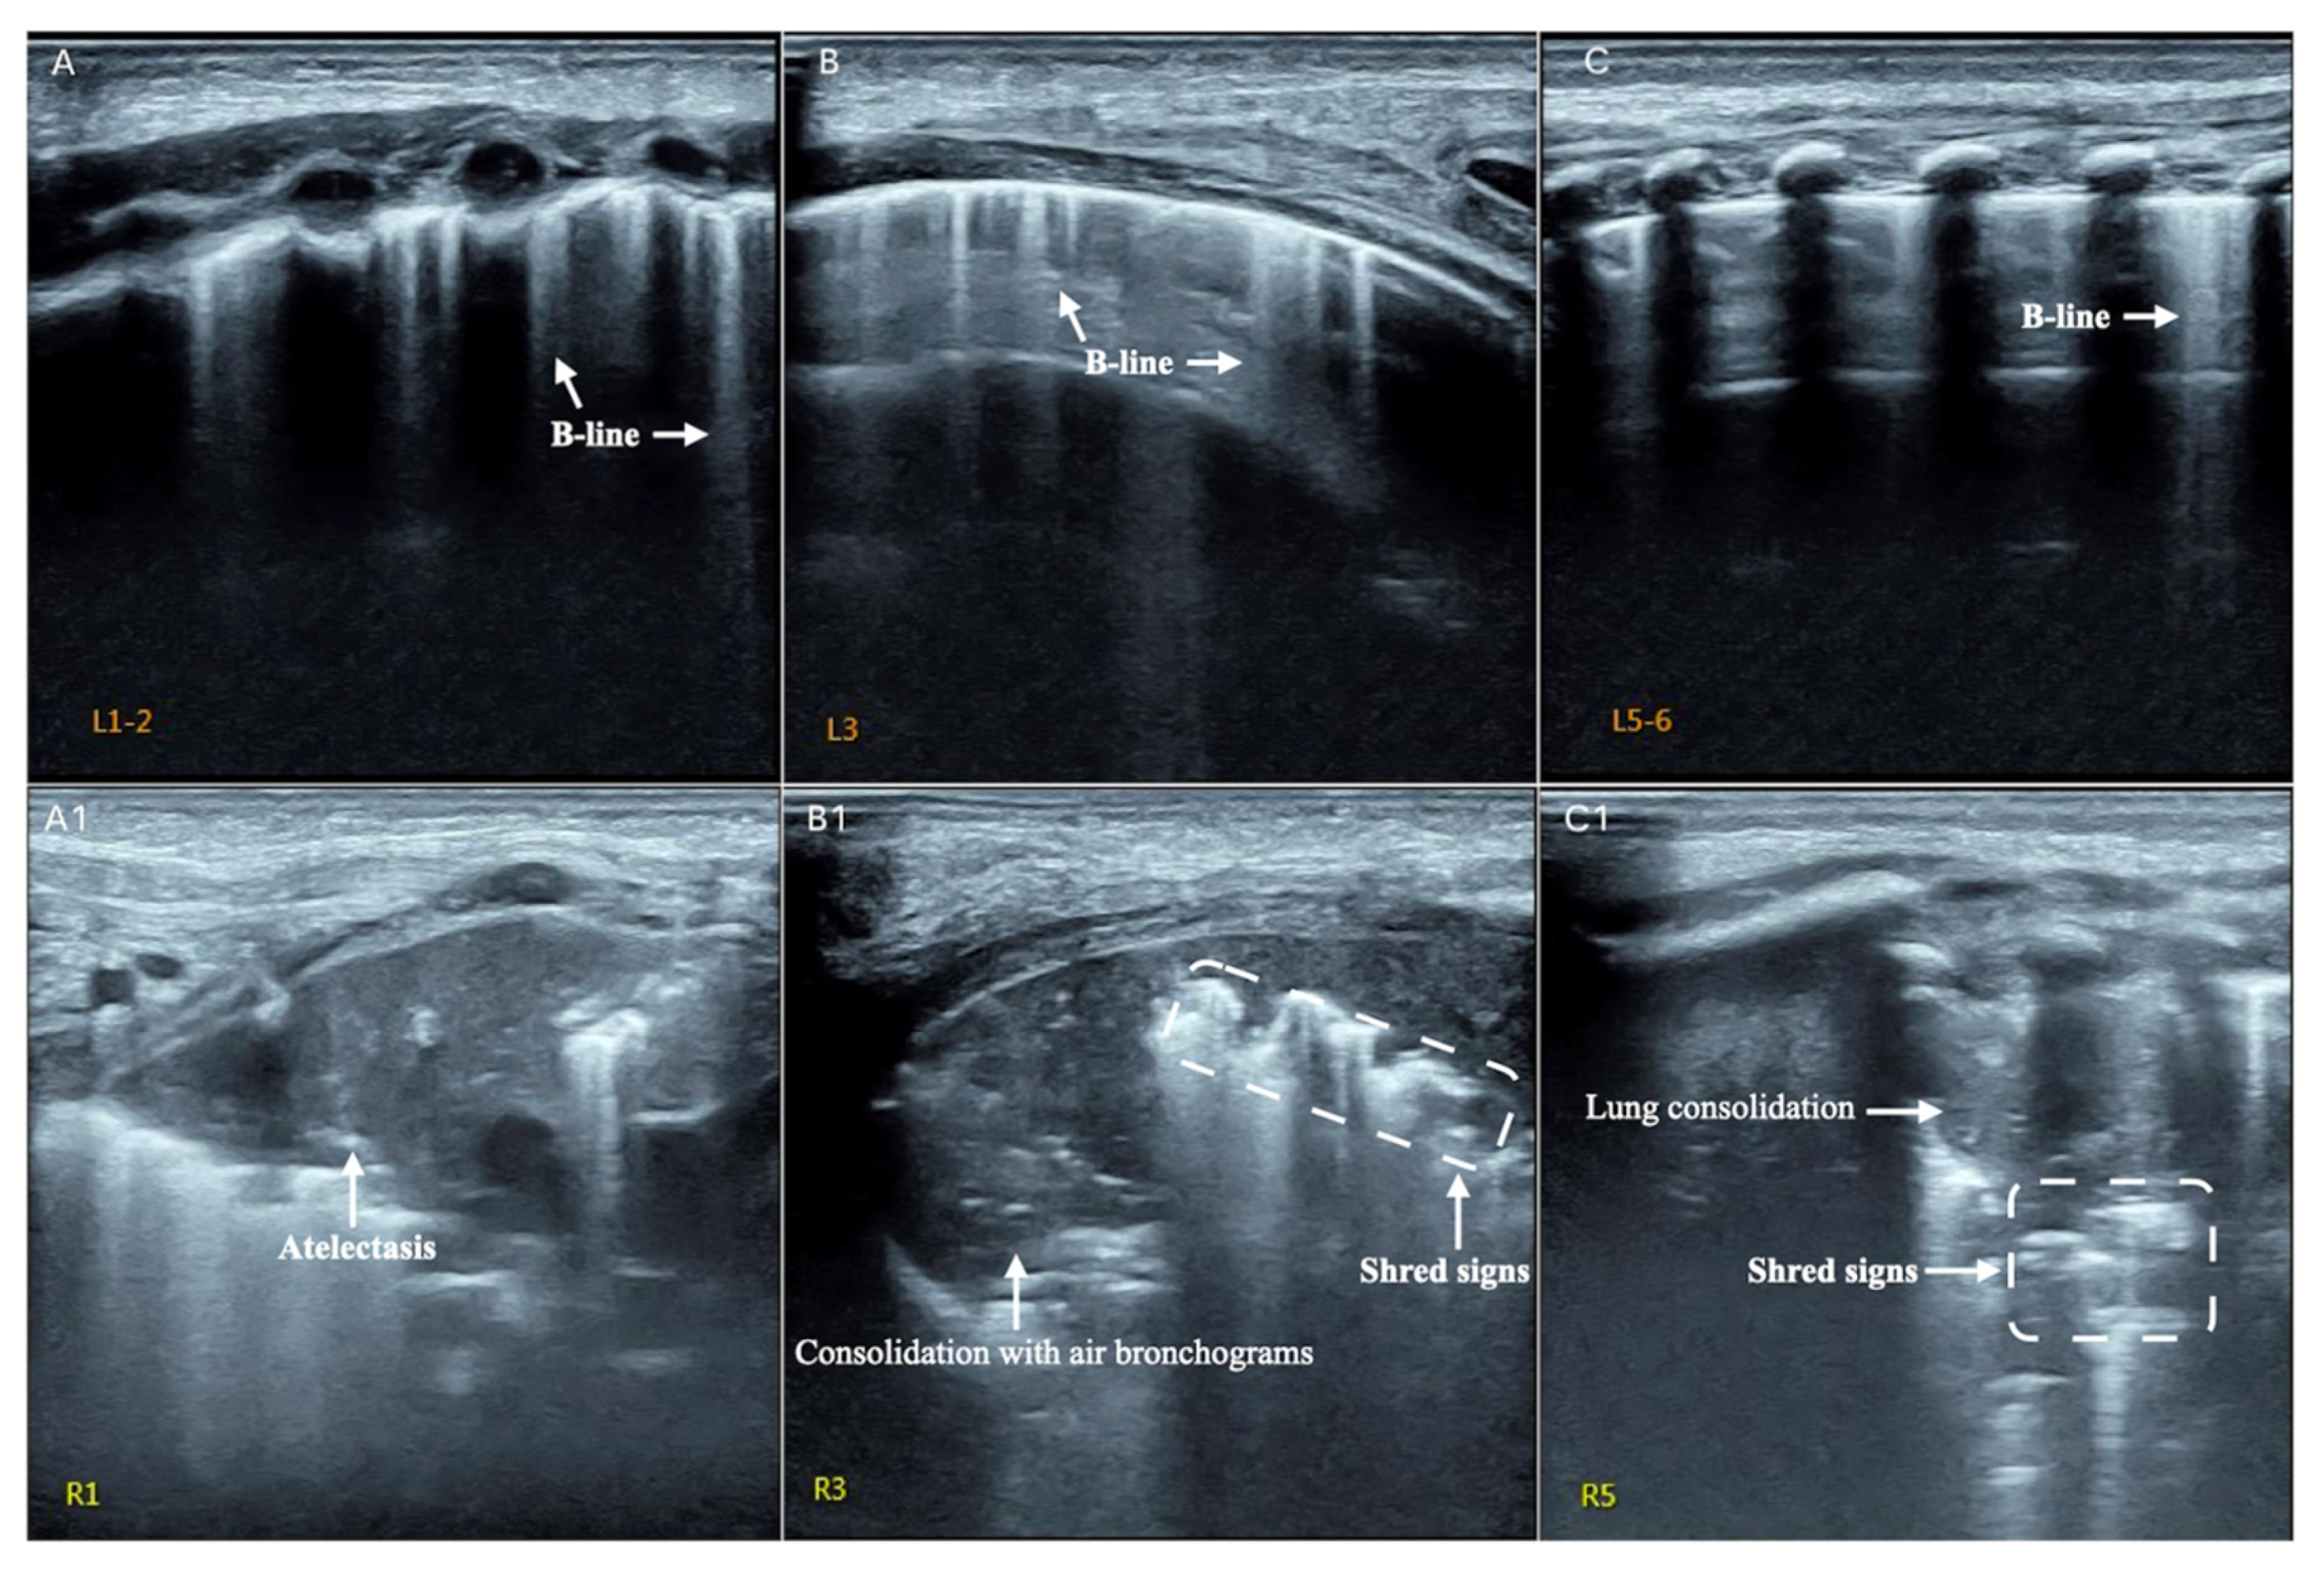

| Consolidation | Area in which lung tissue is de-aerated with density similar to parenchymal tissues [23] |

| Atelectasis | Type of consolidation shown as hyperechogenic tissue structure visualized as solid parenchyma with static air bronchogram [11,24] |

| Cavitation | Solid, hypoechoic, heterogeneous lesions with sharp lobulated margins [11,25] |

| B-lines | Vertical reverberation artefacts from the pleural line to the edge of the scree; laserlike, vertical hyperechogenic artefacts synchronized with pleural line [11,23,27] |

| Pleural irregularities | Reduction or interruption of pleural line [11,28] |

| Sub-pleural nodes/granularities | Hyperechogenic subcentimetric granularities or consolidation under the pleural line [29,30] |